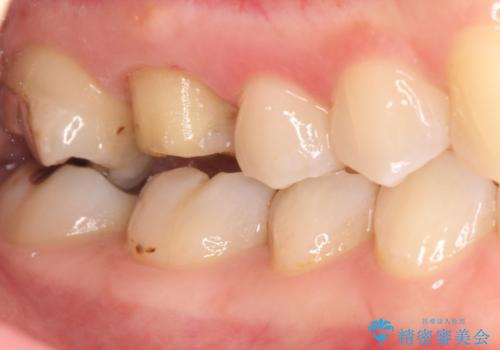

- 右上の歯茎が腫れてきたとのことで来院されました。

右上6番目の歯の位置に腫脹があり、膿も出ている状態でした。

レントゲンを撮影すると、根の先端から膿が排出されていることがわかりました。

根の神経の治療を行い、セラミックを装着する計画としました。